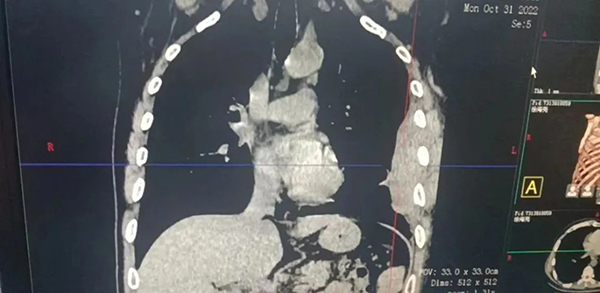

术前影像学表现